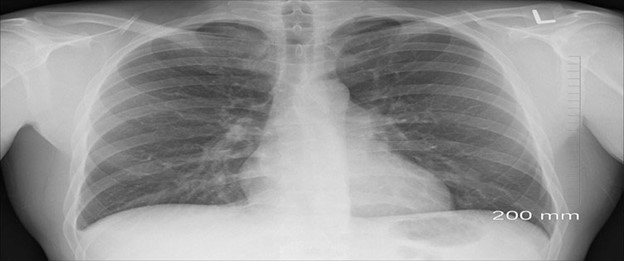

Asbestosis and Silicosis

Since 1986, the Texas Department of State Health Services (DSHS) has tracked asbestosis and silicosis in the state of Texas. Asbestosis is a chronic, fibrotic lung disease. It occurs from long-term inhalation of respirable asbestos fibers. Silicosis is a respiratory disease. It occurs from long-term inhalation of respirable crystalline silica dust.